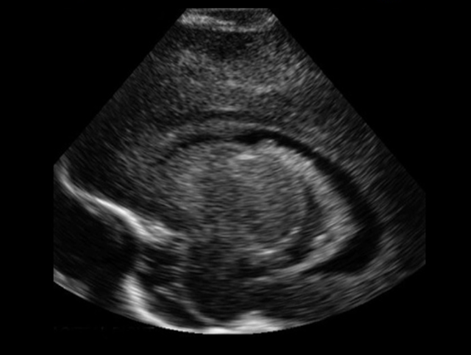

Neonatology Choroid Plexus 4 Image